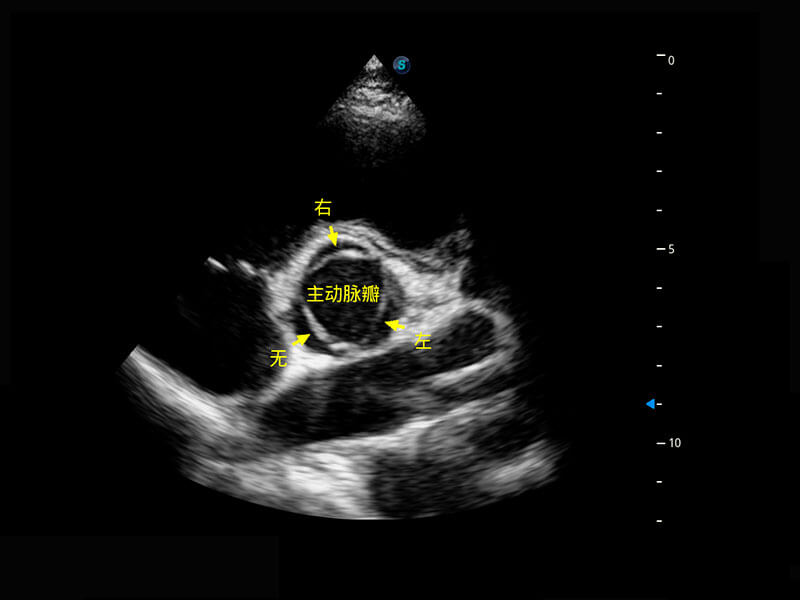

P60搭载一系列胎儿心脏成像技术,实现精细的胎儿心脏评估。

右室双出口

胎心容积成像